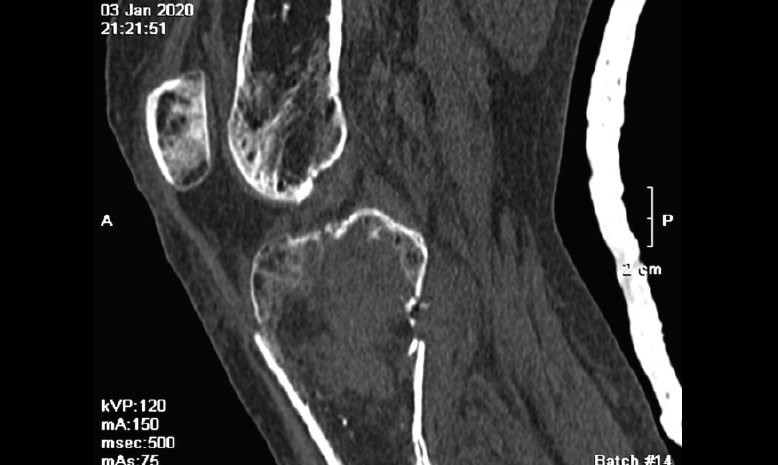

3. Tumores (Figura 26)

Figura 26. Corte de reconstrucción sagital de tomografía axial computarizada de rodilla: masa tumoral en la meseta tibial interna, con fractura patológica epifisaria.